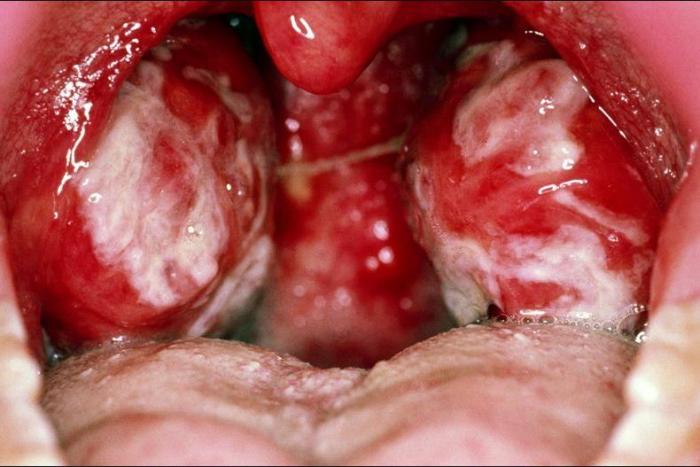

Estudiar los diferentes tipos de enfermedades hemorrágicas virales, arbovirosis, enfermedades herpéticas o virales exantemáticas entre otras